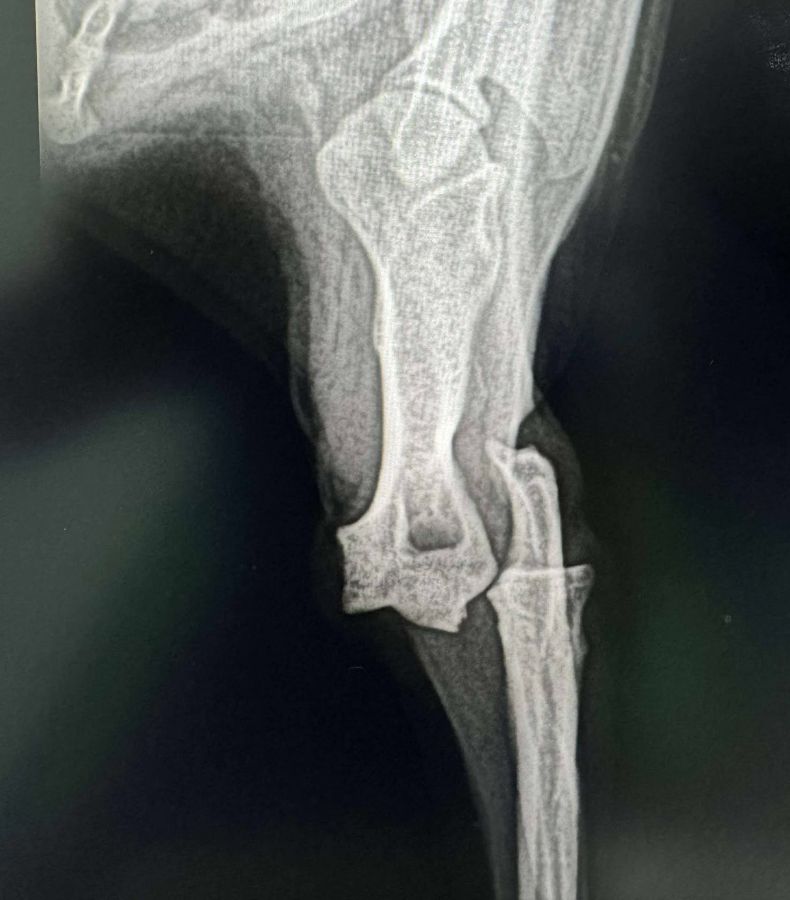

Bei der kleinen MARNIE wurde festgestellt, dass ihr Beinchen weiterhin geschwollen ist. Daher wurde sie in der Klinik gebracht und geröntgt. Dabei zeigte sich, dass das Bein gebrochen ist und nun entsprechend behandelt und operiert werden muss. MARNIE war dabei ganz lieb und hat alles geduldig mitgemacht.